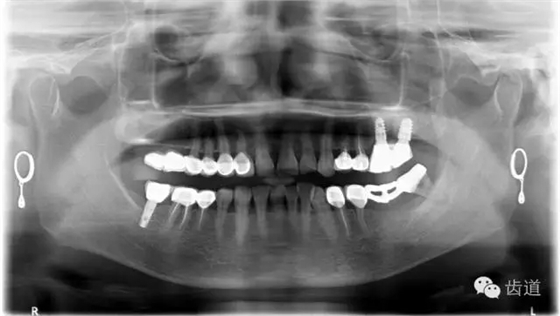

4、 全景片

2、治療后